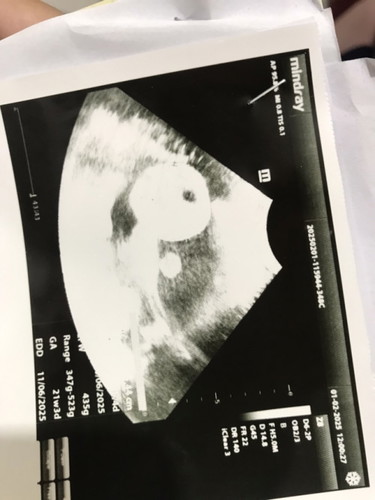

Bun disini ada yg badannya pendek tapi lahiran normal ? Badan saya pendek jadi panggul nya kecil tapi janin posisi nya bagus kepala sudah dibawah dan masuk panggul cuma kata bidan masih ngambang cari jalan lahir ,setiap mlm senam pagi jln kaki kalo mules ujung2nya pgn bab. Saya mah gpp mau normal Sc yg penting sehat selamat cuma suami mertua mau nya normal #bantujawab